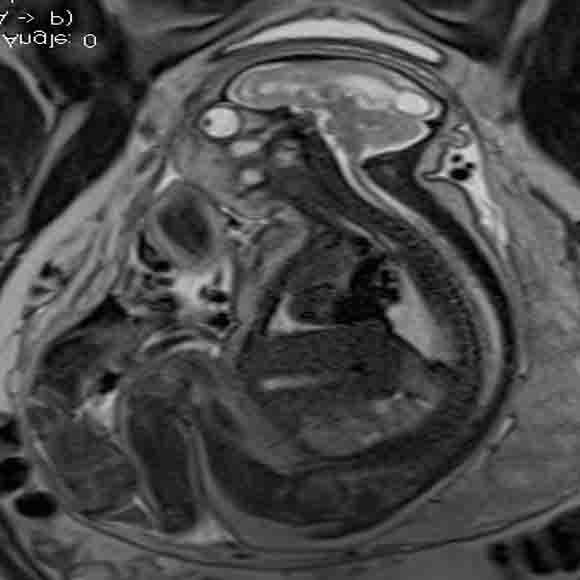

In a third study, ultrasound and fetal MRI were performed on pregnant patients with Zika virus infection at different gestational ages. Once the babies were born, they underwent ultrasound, CT and MRI. The researchers then created 3-D virtual and physical models of the skulls. More than half the babies had microcephaly, brain calcifications and loss of brain tissue volume, along with other structural changes.

"The emergence of Zika virus in the Americas has coincided with increased reports of babies born with microcephaly," said study author Heron Werner Jr., M.D., Ph.D., from the Department of Radiology at Clínica de Diagnóstico por Imagem. "An early diagnosis may help in treating these babies after birth. Moreover, the knowledge of abnormalities present in the central nervous system may give hints about the pathophysiology of the disease."